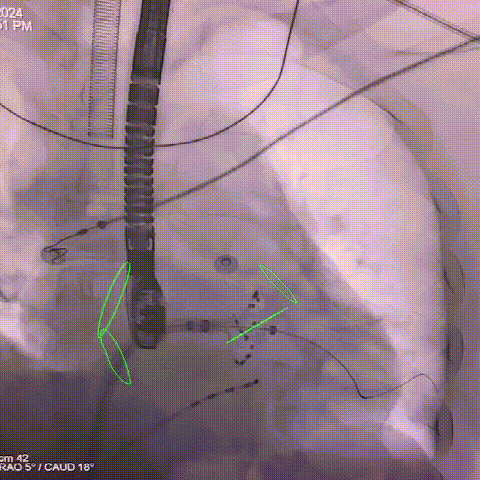

CT与DSA融合

采用图像智能融合系统,将CT与DSA影响实时结合。